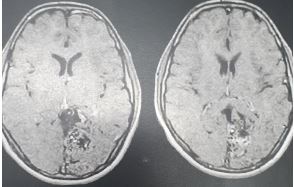

Os pacientes com MAVs comumente se apresentam como tendo tido um sangramento ou seja, com hematomas intra-parenquimatosos, sendo essa a apresentação mais frequente. A taxa de sangramento das MAVs gira em torno de 2 a 4% ao ano. A morbidade e mortalidade após um sangramento, ambas variam de 10 a 30%. A idade de apresentação é em torno dos 33 anos, mas podem ser vistas em crianças e o tratamento deve ser preconizado mais rápido devido a chance maior de sangramentos. Existe o cálculo para estimar o risco acumulado de sangramento (105 – idade do paciente, ou seja, paciente de 10 anos de idade, tem 95% de chance de sangrar). A segunda forma de apresentação mais comum é com crises convulsivas, sendo a forma de apresentação mais comum em crianças. A dor de cabeça pode existir por roubo de fluxo, quando a MAV redireciona sangue para ela mesma.

O diagnóstico das MAVs se faz pela história, exame físico neurológico detalhado e através dos exames complementares. Na tomografia de crânio de entrada, com contraste, e principalmente na ressonância magnética de crânio podemos visualizar vasos irregulares, serpinginosos, veias de drenagem, aneurismas associados. O exame ideal e padrão ouro para o diagnóstico é a arteriografia cerebral digital, exame realizado através de um vasos sanguíneo, colocando contraste no cerebro de forma dinâmico. Nesse exame a drenagem venosa precoce, os aneurismas, nidus, são melhor definidos.